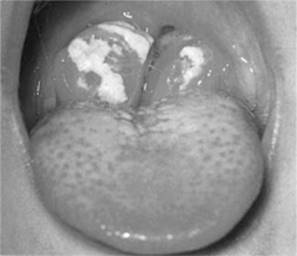

Medical treatment

Penicillin is the first-line choice for treating bacterial tonsillitis (Fig 2.14) and is used for 10 days as a minimum to avoid possible complications relating to systemic streptococcal infections. Beware of prescribing amoxicillin in undiagnosed infectious mononucleosis as this can cause a rash. Treating viral pharyngitis and glandular fever is supportive. Patients with glandular fever should be counselled against participating in contact sports to avoid splenic injury.

Figure 2.14 Bacterial tonsillitis

From Dhillon & East, 2006